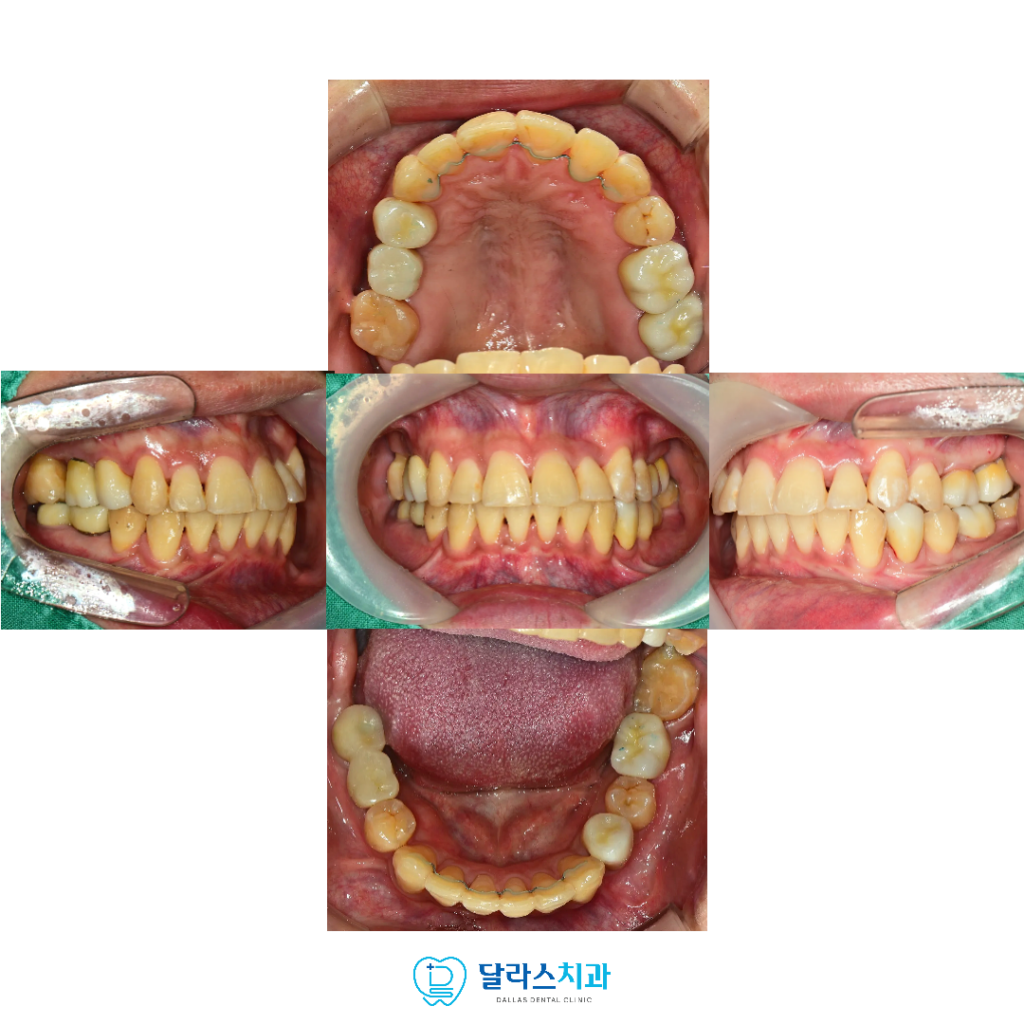

기능적으로 안정적인 교합을 회복하고,

일상에서 편안하게 사용할 수 있는 구강구조를 복원하고 만들어 드리기 위해

앞으로도 한 분 한 분에게 최선을 다해 진료하겠습니다.